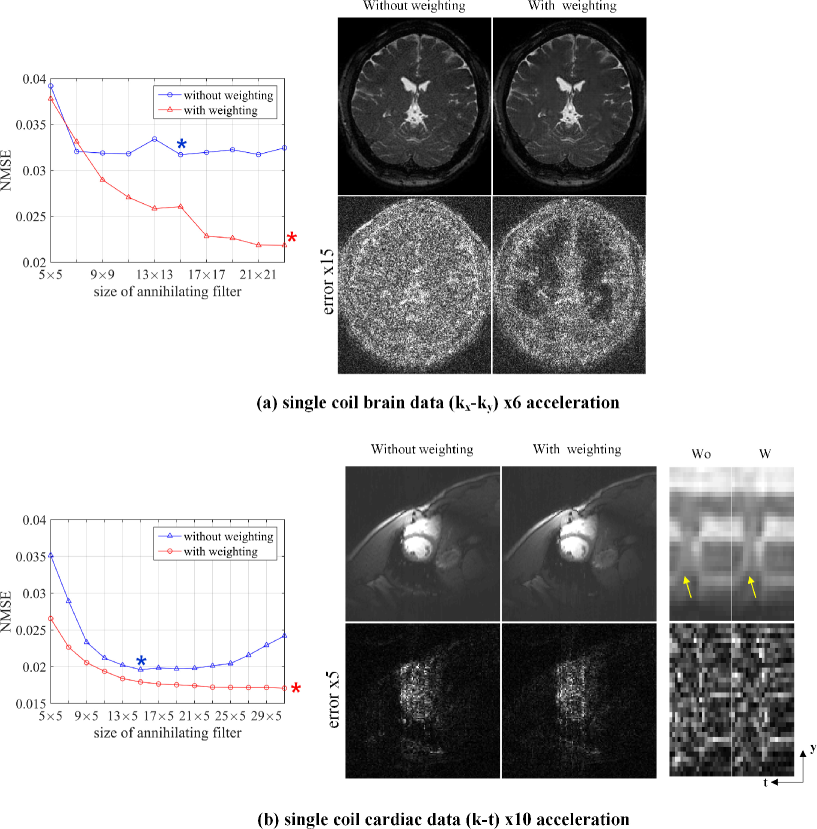

Figures 6(a)(b) illustrate the effects of wavelet weighting schemes. In order to also demonstrate the sensitivity with respect to annihilating filter size, we calculated the NMSE values by changing the filter size. Furthermore, to decouple the confounds originated from different implementation of C-based LORAKS and the ALOHA, the experimental results were generated using the same ALOHA framework with identical parameter setting, except for those related to the weighting. Figure 6(a) showed the single channel brain reconstruction results at the acceleration factor of 6. With weighting, the ALOHA reconstruction was conducted using the following parameters: three levels of pyramidal decomposition, and decreasing LMaFit tolerance values () at each level of the pyramid. In addition, an initial rank estimate for LMaFit started with one and was refined automatically in an increasing sequence, and the ADMM parameter was . Note that these parameters were same with those for (3). For the case of non-weighted implementation of ALOHA, the other parameters are exactly the same except the weighting. The results showed that the NMSE values of the weighted ALOHA are consistently better than those of unweighted ALOHA regardless of the annihilating filter size. Moreover, the NMSE values were not sensitive to the annihilating filter size for the cases of the proposed ALOHA, whose NMSE values converged. The reconstruction results from two implementation at the minimum NMSE values (marked as stars in Figures 6(a)(b) ) were illustrated, which again clearly showed that the residual errors of the weighted ALOHA is significantly smaller than the unweighted version of ALOHA.

Similar results were obtained from the dynamic cardiac imaging data in Figure 6(b). With weighting, the ALOHA reconstruction was conducted using the following parameters: three levels of pyramidal decomposition, and decreasing LMaFit tolerance values () at each level of the pyramid. In addition, an initial rank estimate for LMaFit started with one and was refined automatically in an increasing sequence, and the ADMM parameter was . The reconstruction parameters for the unweighted implementation of ALOHA were exactly the same except the weighting. The results showed that the unweighted ALOHA is very sensitive to the annihilating filter size, which showed the divergent behavior as the filter size increases. However, the proposed weighted ALOHA exhibited the convergent behaviors. This result clearly confirmed Proposition 2.1 saying that the low rank structure is invariant as long as the annihilating filter size is bigger than the transform domain sparsity level. The reconstruction results at the minimum NMSE values clearly showed that the proposed approach provided more clearly transition between diastole and systole phases.